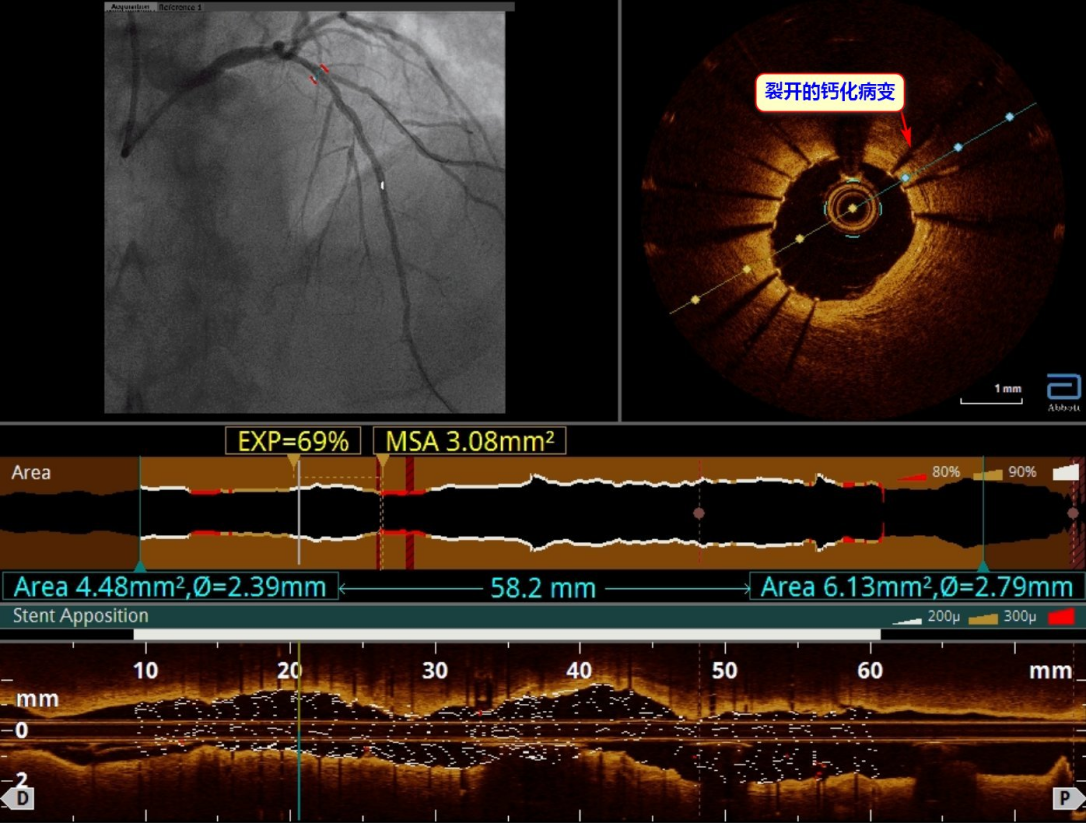

经过综合考虑病情,详细商讨方案,并和家属充分的沟通后,心内科团队采用“振波球囊”为患者进行手术。术中将2.5×12mm的振波球囊(Schockwave)导管送至钙化病变处,给予4个周期的冲击波治疗。术后复查OCT,提示环状钙化被碎裂,裂痕明显,血管腔明显增大,这代表像“石头”一样的钙化斑块被“振”断了,“难点”被攻克后,心内科团队顺利将支架推送到位,精准释放,扩张充分,贴壁良好。术后,王大爷表示胸闷症状明显缓解,已康复出院。